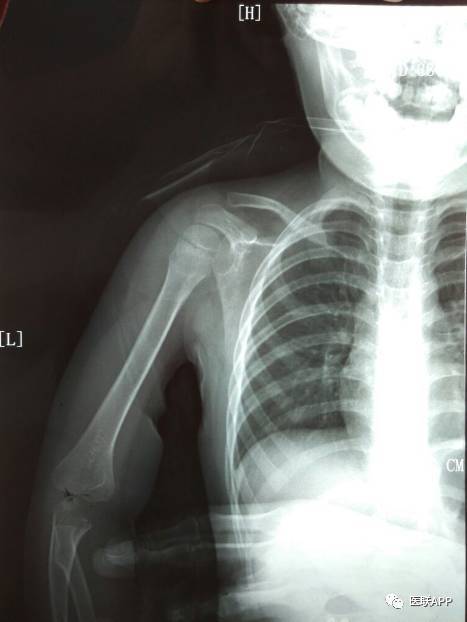

锁骨骨折

小儿锁骨青枝骨折一例